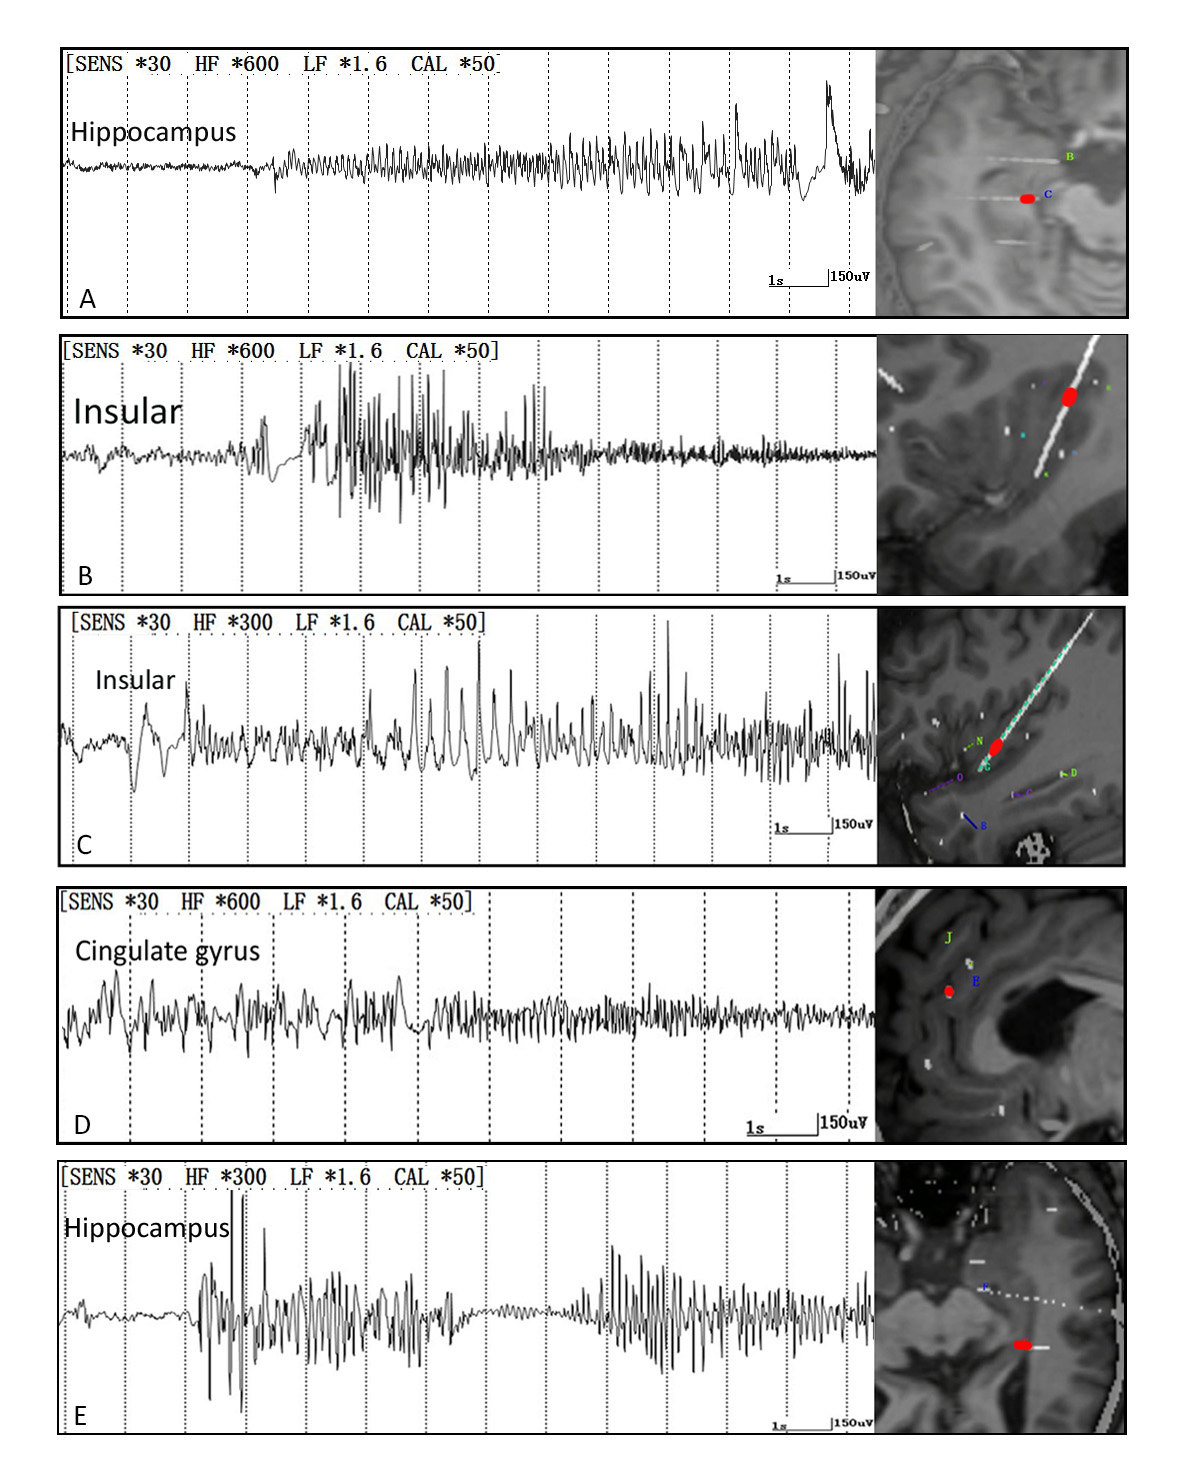

肌电图专辑【九】异常针极肌电图(1)

肌电图专辑九异常针极肌电图2

肌电图专辑【九】异常针极肌电图(3)

肌电图专辑九异常针极肌电图3

轻度收缩时的异常肌电图大力收缩时的各种不同的募集现象图参考文献